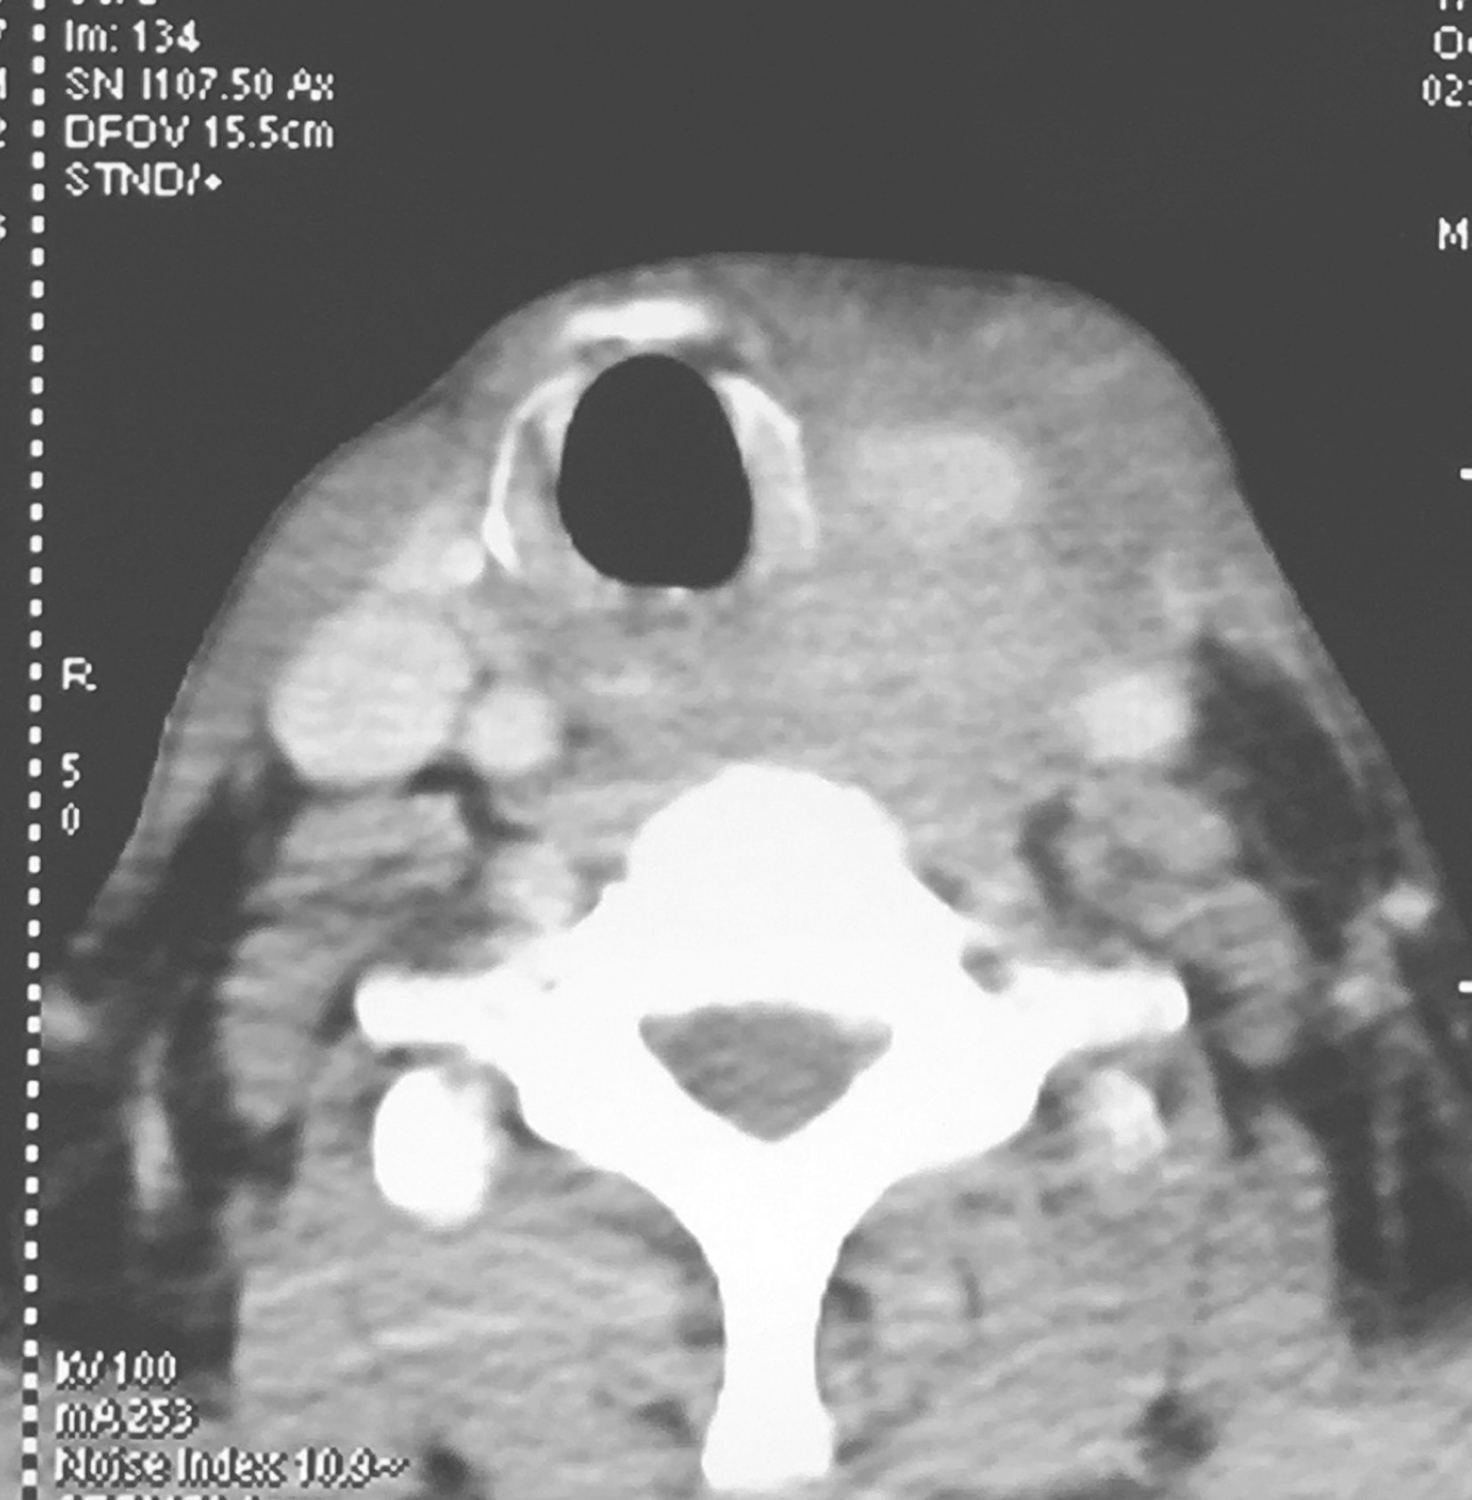

3.颈胸强化CT检查

①下咽部左梨状窝区可见软组织密度影,增强扫描可强化,向内累及左侧半喉,侵犯会厌前间隙、声门旁间隙,肿瘤侵透甲状软骨板、舌骨、累及咽侧壁及下咽后壁(图1、图2),向下累及环后区及颈段食管,向外侵犯喉外肌肉及颈前软组织。颈动脉鞘周围多枚肿大淋巴结,部分融合,边界不清,与咽喉肿瘤及颈前肌肉融合,右侧甲状腺受侵(图3),颈内静脉闭塞(图4),颈总动脉与肿瘤边界不清。右侧颈鞘周围也可见多枚肿大淋巴结,增强扫描可见强化。②双肺纹理增粗,双肺野及纵隔内未见异常。

影像学诊断:符合下咽部恶性肿瘤累及喉,双颈部多发淋巴结转移表现。

图2向内累及左侧半喉,侵犯会厌前间隙、声门旁间隙,肿瘤侵透甲状软骨板、舌骨、累及咽侧壁及下咽后壁

图3颈胸部增强CT示颈动脉鞘周围多枚肿大淋巴结